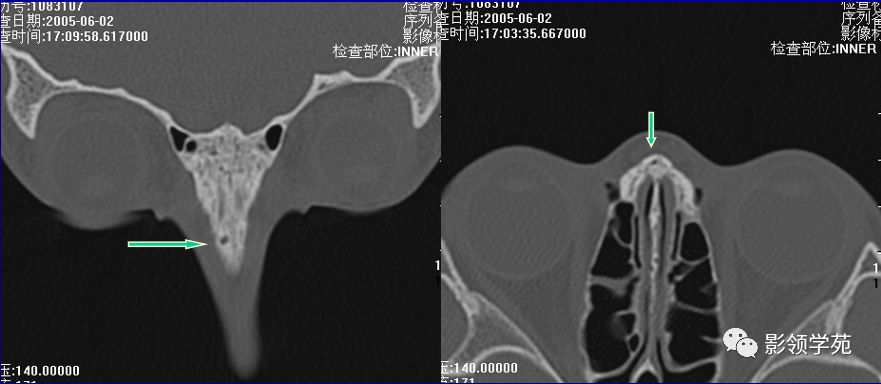

双侧鼻骨骨折

鼻中隔骨折